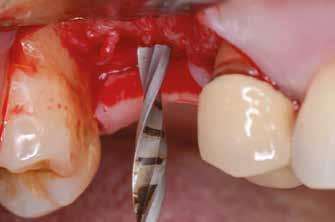

Sebészeti eljárás

Az eljárást helyi érzéstelenítés mellett végeztük (4%-os articaine-hidroklorid 1:100 000 adrenalinnal). Papillakímélő, U alakú palatális bemetszést végeztünk, teljes vastagságú nyálkahártyalebeny preparálás történt, a lebenyt bukkálisan feltekertük (5. ábra). A lebeny bukkálisan feltekert részén de-epitelizációt végeztük el, amellyel kompenzálni tudtuk a bukkális lágyszöveti defektust. Szakaszos előfúrást végeztünk, és a bredent copaSKY 4x10 implantátumot 30 Ncm behajtási nyomatékkal helyeztük be (6. ábra). Az implantátumot 1 mm-re szubkresztálisan helyeztük be, hogy később szélesebb emergenciaprofilt tudjunk kialakítani (7. ábra). Az egyedi ínyformázó úgy készült, hogy kompozitot vittünk fel a titánbázisra, és így formáztuk a lágyszöveteket a transzgingivális gyógyulási fázis során (8. ábra). Az egyéni ínyformázó tulipán formájú, hogy kialakítsa a kívánt emergenciaprofilt. A lágyszövetet feszülésmentesen zártuk #6/0 nem felszívódó, monofil fonallal (Optilene, B. Braun Deutschland; 9. a–b. ábra). Posztoperatív röntgenfelvétel készült, ami alapján az implantátum a szomszédos fogakkal párhuzamos elhelyezést mutatott (10. ábra). Posztoperatív utasításokat adtunk a páciensnek a műtéti terület körüli szájhigiénia fenntartása érdekében. A beavatkozást követő egy héttel a varratokat eltávolítottuk, és a kezelt terület kielégítő gyógyulást mutatott (11. ábra). A 4 hónap utáni késleltetett terhelést a páciens kívánsága szerint terveztük.

1. ábra: Műtét előtti fogászati panorámafelvétel, amelyen a hiányzó felső állcsont jobb első premolárisát és a szabad véggel rendelkező hidat láthatjuk. — 2. ábra: Az implantátum méreteinek megtervezése CBCT-vel. 3. ábra: Bukkális lágyrészdefektus. — 4. ábra: A biológiai szélesség értékelése a vertikális lágyszövetvastagság alapján. 5. ábra: Palatinális „tekercslebeny” – Palatal roll flap. — 6. ábra: Bredent medical copaSKY 4x10 implantátumbeültetés. 7. ábra: Szubkresztális implantátumbeültetés a várható biológiai szélességnek megfelelően.